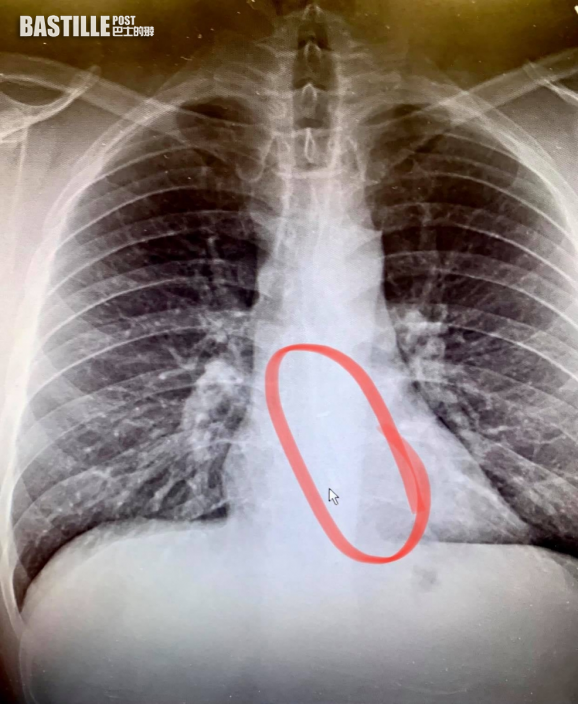

不少人會戴著無線耳機邊聽歌邊入睡,但其實也有潛在風險。美國一名男子日前起床喝水時感到喉嚨不適,又發現戴着睡覺的AirPods不見了一隻,他求醫照X光後,發現耳機竟然卡在食道壁上,當時醫生還好奇他為何沒有出現疼痛,形容情況非常罕見,他最後接受緊急內窺鏡手術將耳機取出。

Bradford聽罷認為也有此可能性,曾使用「Find my AirPods」的功能尋找,但耳機當時已經無電,所以沒有反應,「如果從喉嚨聽到小小的嗶嗶聲,那會是我一生最奇怪的時刻」。妻子Heather隨即帶他到醫院急症室求診,照X光後果然發現在食道下方有一隻AirPods,醫生於是馬上為他做緊急內窺鏡手術將耳機取出。

醫生直言事件難以置信,指出耳機牢牢卡在食道壁上,雖有東西阻塞卻沒有引起疼痛及嚴重不適,情況非常罕見。而Bradford也慨嘆自己好運:「耳機有可能進入我的氣管和肺部,阻塞我的呼吸。」